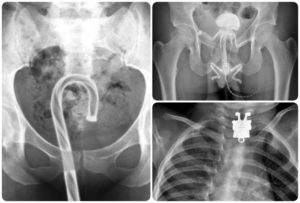

Врач может отыскать инородное тело в заднем проходе во время пальцевого исследования прямой кишки. Также инородные тела определяются путем рентгенологического исследования.

Для того, чтобы выяснить, повреждена или нет стенка толстой кишки, проводится инструментальное обследование — ректороманоскопия и рентгенография (ирригоскопия).

Если пациент указывает на наличие инородного предмета в прямой кишке, при помощи пальцевого обследования возможно определить его местонахождение, форму, размеры и подвижность.

В некоторых случаях посредством пальцевого исследования удается извлечь инородный предмет, так как чаще всего инородное тело располагается в среднем сегменте прямой кишки.

Для выявления постороннего предмета в прямой кишке может потребоваться использование ректальных зеркал или аноскопии.

Затем может потребоваться обследование с помощью ректоскопа, а также рентген брюшной полости для определения точного расположения инородного предмета.